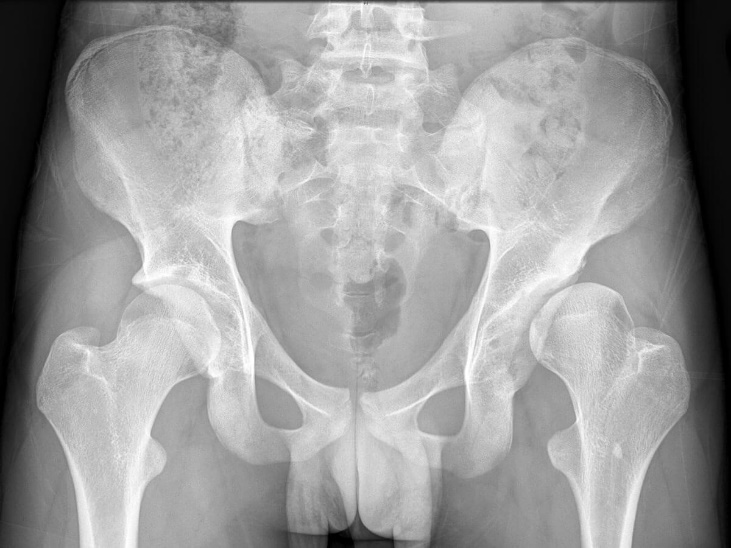

Natural progression of dysplasia with subluxation to severe arthritis

Natural progression of dysplasia with subluxation to severe arthritis.